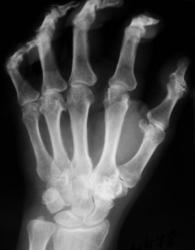

Катенёв Валенти... Дата публикации 25.06.2009, 00:50 Пациент направлен терапевтом в рентгеновский кабинет "на рентгенографию кистей", с диагнозом "Ревматоидный артрит". Ваше мнение коллеги? Чт, 25/06/2009 - 07:54 #1 Андрей Юрьевич Не на сайте Был на сайте: 2 недели 2 дня назад Зарегистрирован: 16.11.2008 - 22:16 Публикации: 18098 Сложно сказать, нет решающего рентген-признака: периартикуллярного остеопороза. В данном случае надежда на лабораторные данные, это ведь и подагрой (см. ниже http://www.radiomed.ru/cases/podaghrichieskii-artrit ) может быть. Андрей Юрьевич Чт, 25/06/2009 - 18:13 #2 OPEXOB Не на сайте Был на сайте: 9 лет 11 месяцев назад Зарегистрирован: 26.07.2008 - 10:02 Публикации: 280 Ревматоидный полиартрит, 4 рентгенологическая стадия. Судя по положению кистей, особенно дистальных фаланг имеет место контрактура данных сочленений. Анализы? СОЭ? Клиника? Чт, 25/06/2009 - 18:45 #3 Андрей Юрьевич Не на сайте Был на сайте: 2 недели 2 дня назад Зарегистрирован: 16.11.2008 - 22:16 Публикации: 18098 ///Анализы? СОЭ? Клиника?/// Выходит Петр. Он ужасен, Движенья быстры, Он прекрасен, Он весь как божия гроза (с) Андрей Юрьевич Чт, 25/06/2009 - 19:20 #4 OPEXOB Не на сайте Был на сайте: 9 лет 11 месяцев назад Зарегистрирован: 26.07.2008 - 10:02 Публикации: 280 Ха,ха, очень смешно!

Сложно сказать, нет решающего рентген-признака: периартикуллярного остеопороза. В данном случае надежда на лабораторные данные, это ведь и подагрой (см. ниже http://www.radiomed.ru/cases/podaghrichieskii-artrit ) может быть.

Ревматоидный полиартрит, 4 рентгенологическая стадия. Судя по положению кистей, особенно дистальных фаланг имеет место контрактура данных сочленений.